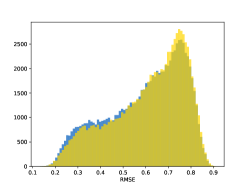

To visualise similarity metrics that compare image pairs (RMSE, SRE, SSIM) two metric distributions are generated: intra-similarity and inter-similarity. For each compared sample 300 random images are selected. The inter-similarity distribution is calculated for each image pair combination from both compared samples e.g. generated images of COVID-19 and real images of COVID-19. For the intra-similarity, all pairs of images in a single sample e.g real images of COVID-19 are considered. By comparing the shape of intra-similarity for the training subsample (Dataset) with the inter-similarity of training and generated samples the quality of the generated sample can be judged. It is also possible to compare in this way between the four image classes present in the dataset. The resulting distributions of inter-similarity of COVID-19 and the three remaining classes are compared in Fig. 4 to distributions of intra-similarity of the COVID-19 sample for each metric. All metrics, as expected based on available medical evidence Rubin et al. (2020), indicate that there are visible differences not only between COVID-19 and normal samples but also between viral pneumonia and lung opacity. Therefore, all classes should be distinguishable.

To visualise differences between synthetic and real samples distributions are generated for each of the RMSE, SRE and SSIM metrics: intra-similarity and inter-similarity. For each compared sample 300 random images are selected. The inter-similarity distribution is calculated for each image pair combination from both compared samples e.g. generated images of COVID-19 and real images of COVID-19. For the intra-similarity, all pairs of images in a single sample e.g real images of COVID-19 are considered. The distributions for generated samples describe very well the distributions for corresponding real images as shown in Fig. 6.

The quality of generated images is also confirmed with classical similarity metrics. The distributions of those similarity measures between generated and real images are compared for each sample with the distribution obtained within the real samples 6. The distributions for generated samples describe very well the distributions for corresponding real images. For an example see the results for the SSIM metric presented in Fig. 10. The small visible differences are almost insignificant compared to differences observed between the classes in Fig. 4.